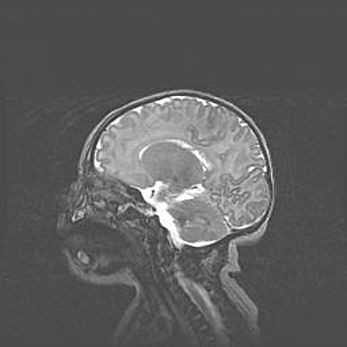

Сообщающаяся гидроцефалия. Кистозная энцефаломаляция головного мозга.

Возраст: 3 месяца 4 дня

Вес: 3100 г

Пол: женский

Окружность головы: 34 см

Срок гестации: 31 неделя

Кистозная энцефаломаляция головного мозга - одна из форм поражения головного мозга в детском возрасте. Характеризуется возникновением множественных и распространённых кист в коре, белом веществе и подкорковых образованиях головного мозга у плодов, новорождённых и детей раннего возраста. Развитие кистозной энцефаломаляции связано с внутриутробной асфиксией и гипотонией, родовой травмой, тромбозом синусов, пороками развития сосудов, инфекциями, сепсисом и другими причинами. Наиболее значимые инфекционные агенты: вирусы простого герпеса, цитомегалии, краснухи, токсоплазмы, энтеробактерии, золотистый стафилококк и другие.